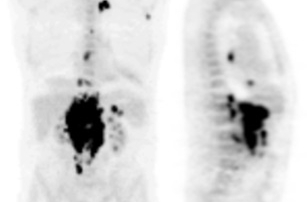

TEP-FDG : persistance d’un discret hypermétabolisme en regard de l’adénomégalie

axillaire droite isolée SUV max 2.0 , SUV max du bruit de fond avoisinant à 0.9.

Absence d’hypermétabolisme suspect au niveau des autres aires ganglionnaires.

Réponse métabolique partielle axillaire droite et réponse métabolique complète

sur les autres territoires.